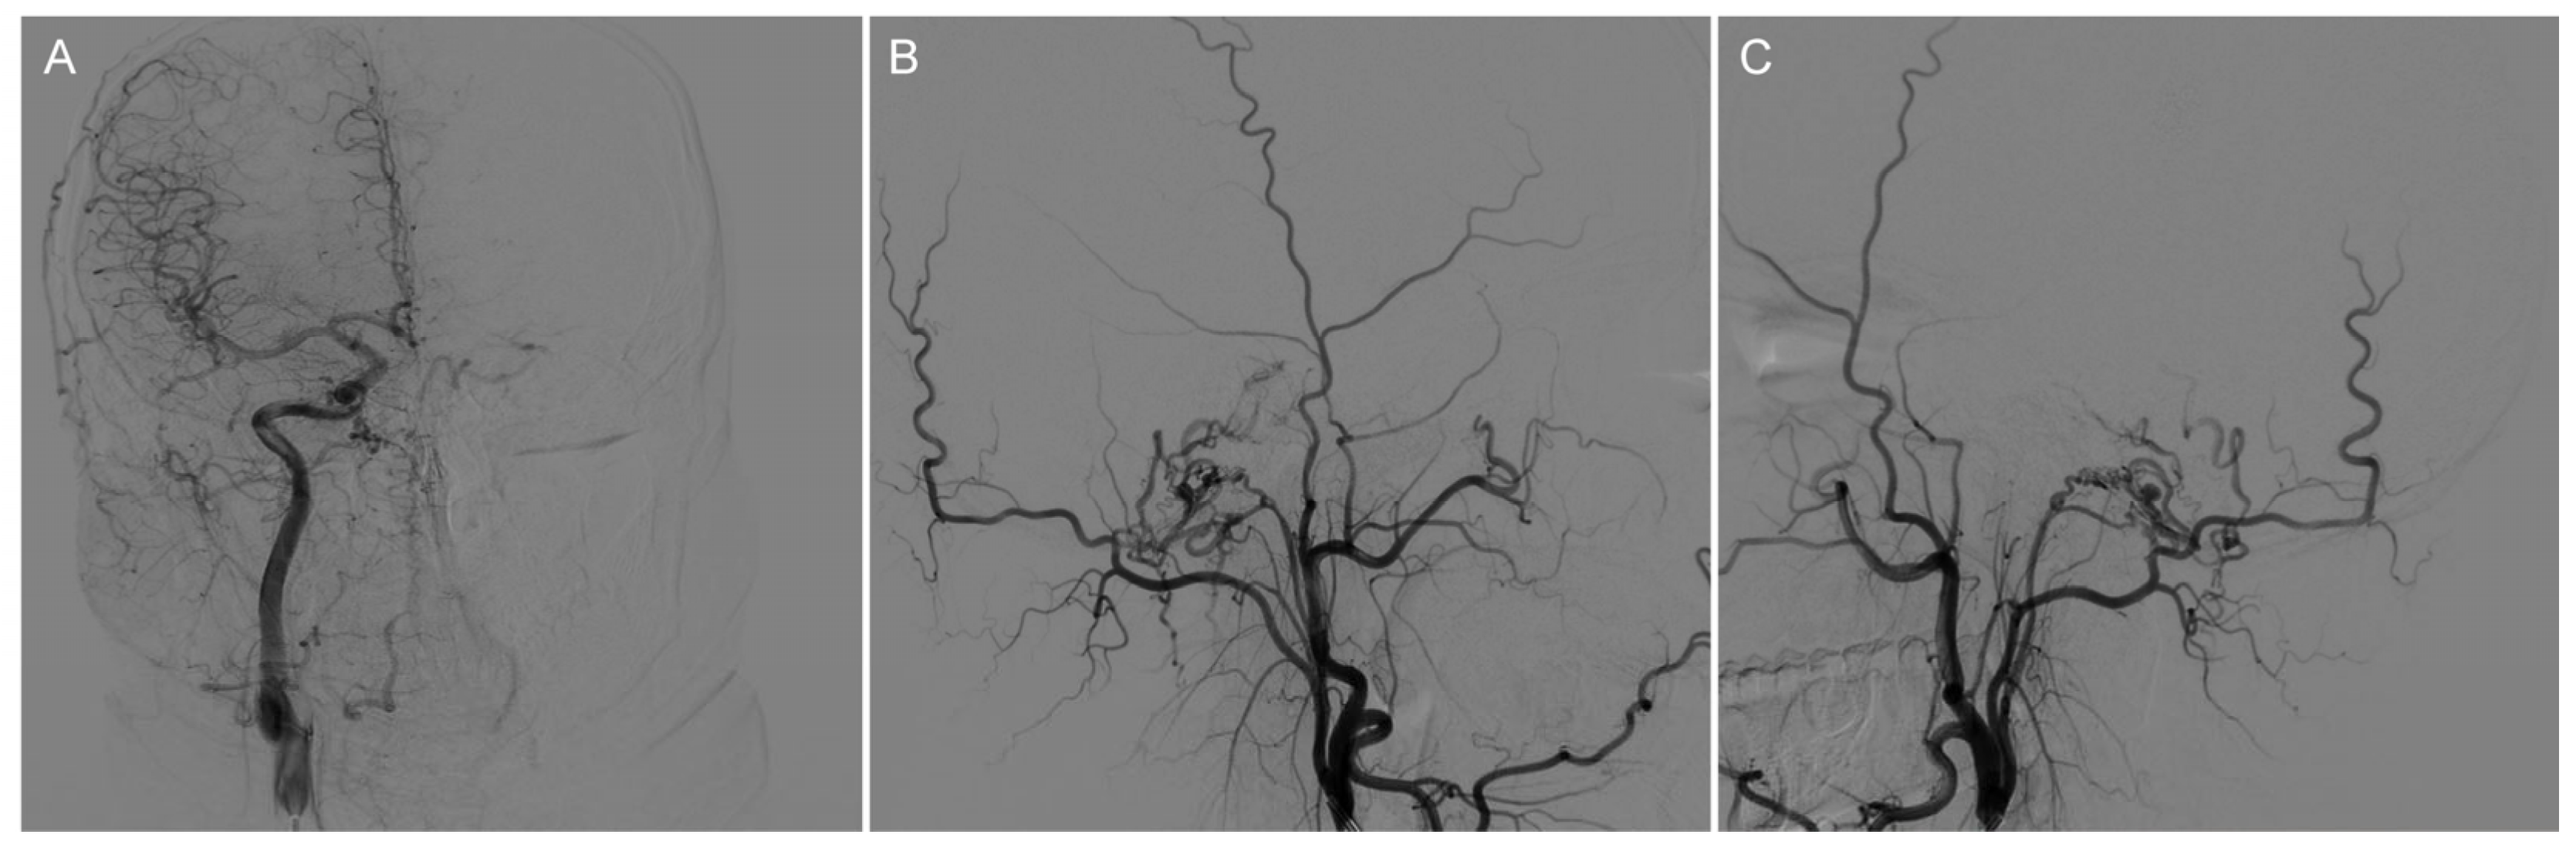

We ruled out the possibility of an intracranial hemorrhagic lesion, which is often associated with increased intracranial pressure, severe headache, or loss of consciousness [6,7,8]. To further clarify the diagnosis, we performed a digital subtraction angiography (DSA) examination, which showed that our preoperative diagnosis was inaccurate and the mass lesion was not caused by a tumor. DSA examinations revealed CCJAVFs, where the right ascending pharyngeal artery acted as the donor artery, and the spinal veins and the occipital cortical veins acted as the drainage veins (Figure 2A–C). The treatment modality should be decided by the anatomical structure and the position of AVF, for which the operation or the intravascular intervention was suitable. The DSA examination suggested that a craniotomy would be unnecessary and that this patient only required management of the arteriovenous fistula. Based on these preoperative findings, an endovascular intervention was performed. A 6F guide sheath was placed through a puncture in the right femoral artery, and a 6F guiding catheter was applied for imaging. The 6F guide catheter was placed at the beginning of the right external carotid artery with the assistance of a guidewire under the roadmap. The contrast media determined that there was no spasm of the vessel. A microcatheter was placed into the site close to the fistula under the road map for embolization, and a spring coil was placed in the superior trunk of the right ascending pharyngeal artery to reduce blood flow and further thrombotic occlusion (Figure 3A,B). The angiogram showed a significant decrease in the blood flow in the superior trunk of the ascending pharyngeal artery. Then, an Onyx biologic gel was injected slowly and intermittently into the upper and lower trunks of the ascending pharyngeal artery through the microcatheter (Figure 3C,D). The diffusion and regurgitation of the Onyx biologic gel were repeatedly observed via microcatheter imaging until the branch at the fistula was completely embolized. The angiogram showed a complete non-visualization of the supply artery and drainage vein, and all intracranial branches were present. Five days after surgery, the DSA analysis showed a complete embolization of the fistula (Figure 4A). The CT examinations showed a lamellar, slightly hypointense shadow in the brainstem, without hemorrhage or ischemia (Figure 4B). The MRI examinations showed lamellar, slightly long T1 and slightly long T2 signals in the brainstem, with a maximum cross-section of about 10 mm × 8 mm. The brainstem mass lesion after treatment was reduced when compared to that before treatment (Figure 4C,D). It is important to note that embolization may pose an additional risk. Dimethyl sulfoxide injection is required prior to embolization and may have potential neurotoxicity. Access vascular injury may occur during embolization. If the biogel enters a vessel other than the lesion site, it may cause cerebral infarction. During embolization, hemodynamic changes also require attention. In fact, immediately after the patient’s surgery was completed, we transferred the patient to the ICU for detailed monitoring as well as an assessment of the patient’s status. After 7 days of monitoring, we confirmed that the patient had no complications and then transferred him to the general ward. The patient recovered well after the operation, and his headaches and hoarseness decreased. He was discharged with a Karnofsky score of 90.

Figure 2.

Preoperative DSA of the AVF showed that the right ascending pharyngeal artery served as the donor artery, and the spinal veins and occipital cortex veins served as the draining veins. (A) Preoperative imaging (frontal view); (B) Preoperative imaging (right-sided view); (C) Preoperative imaging (left-sided view).